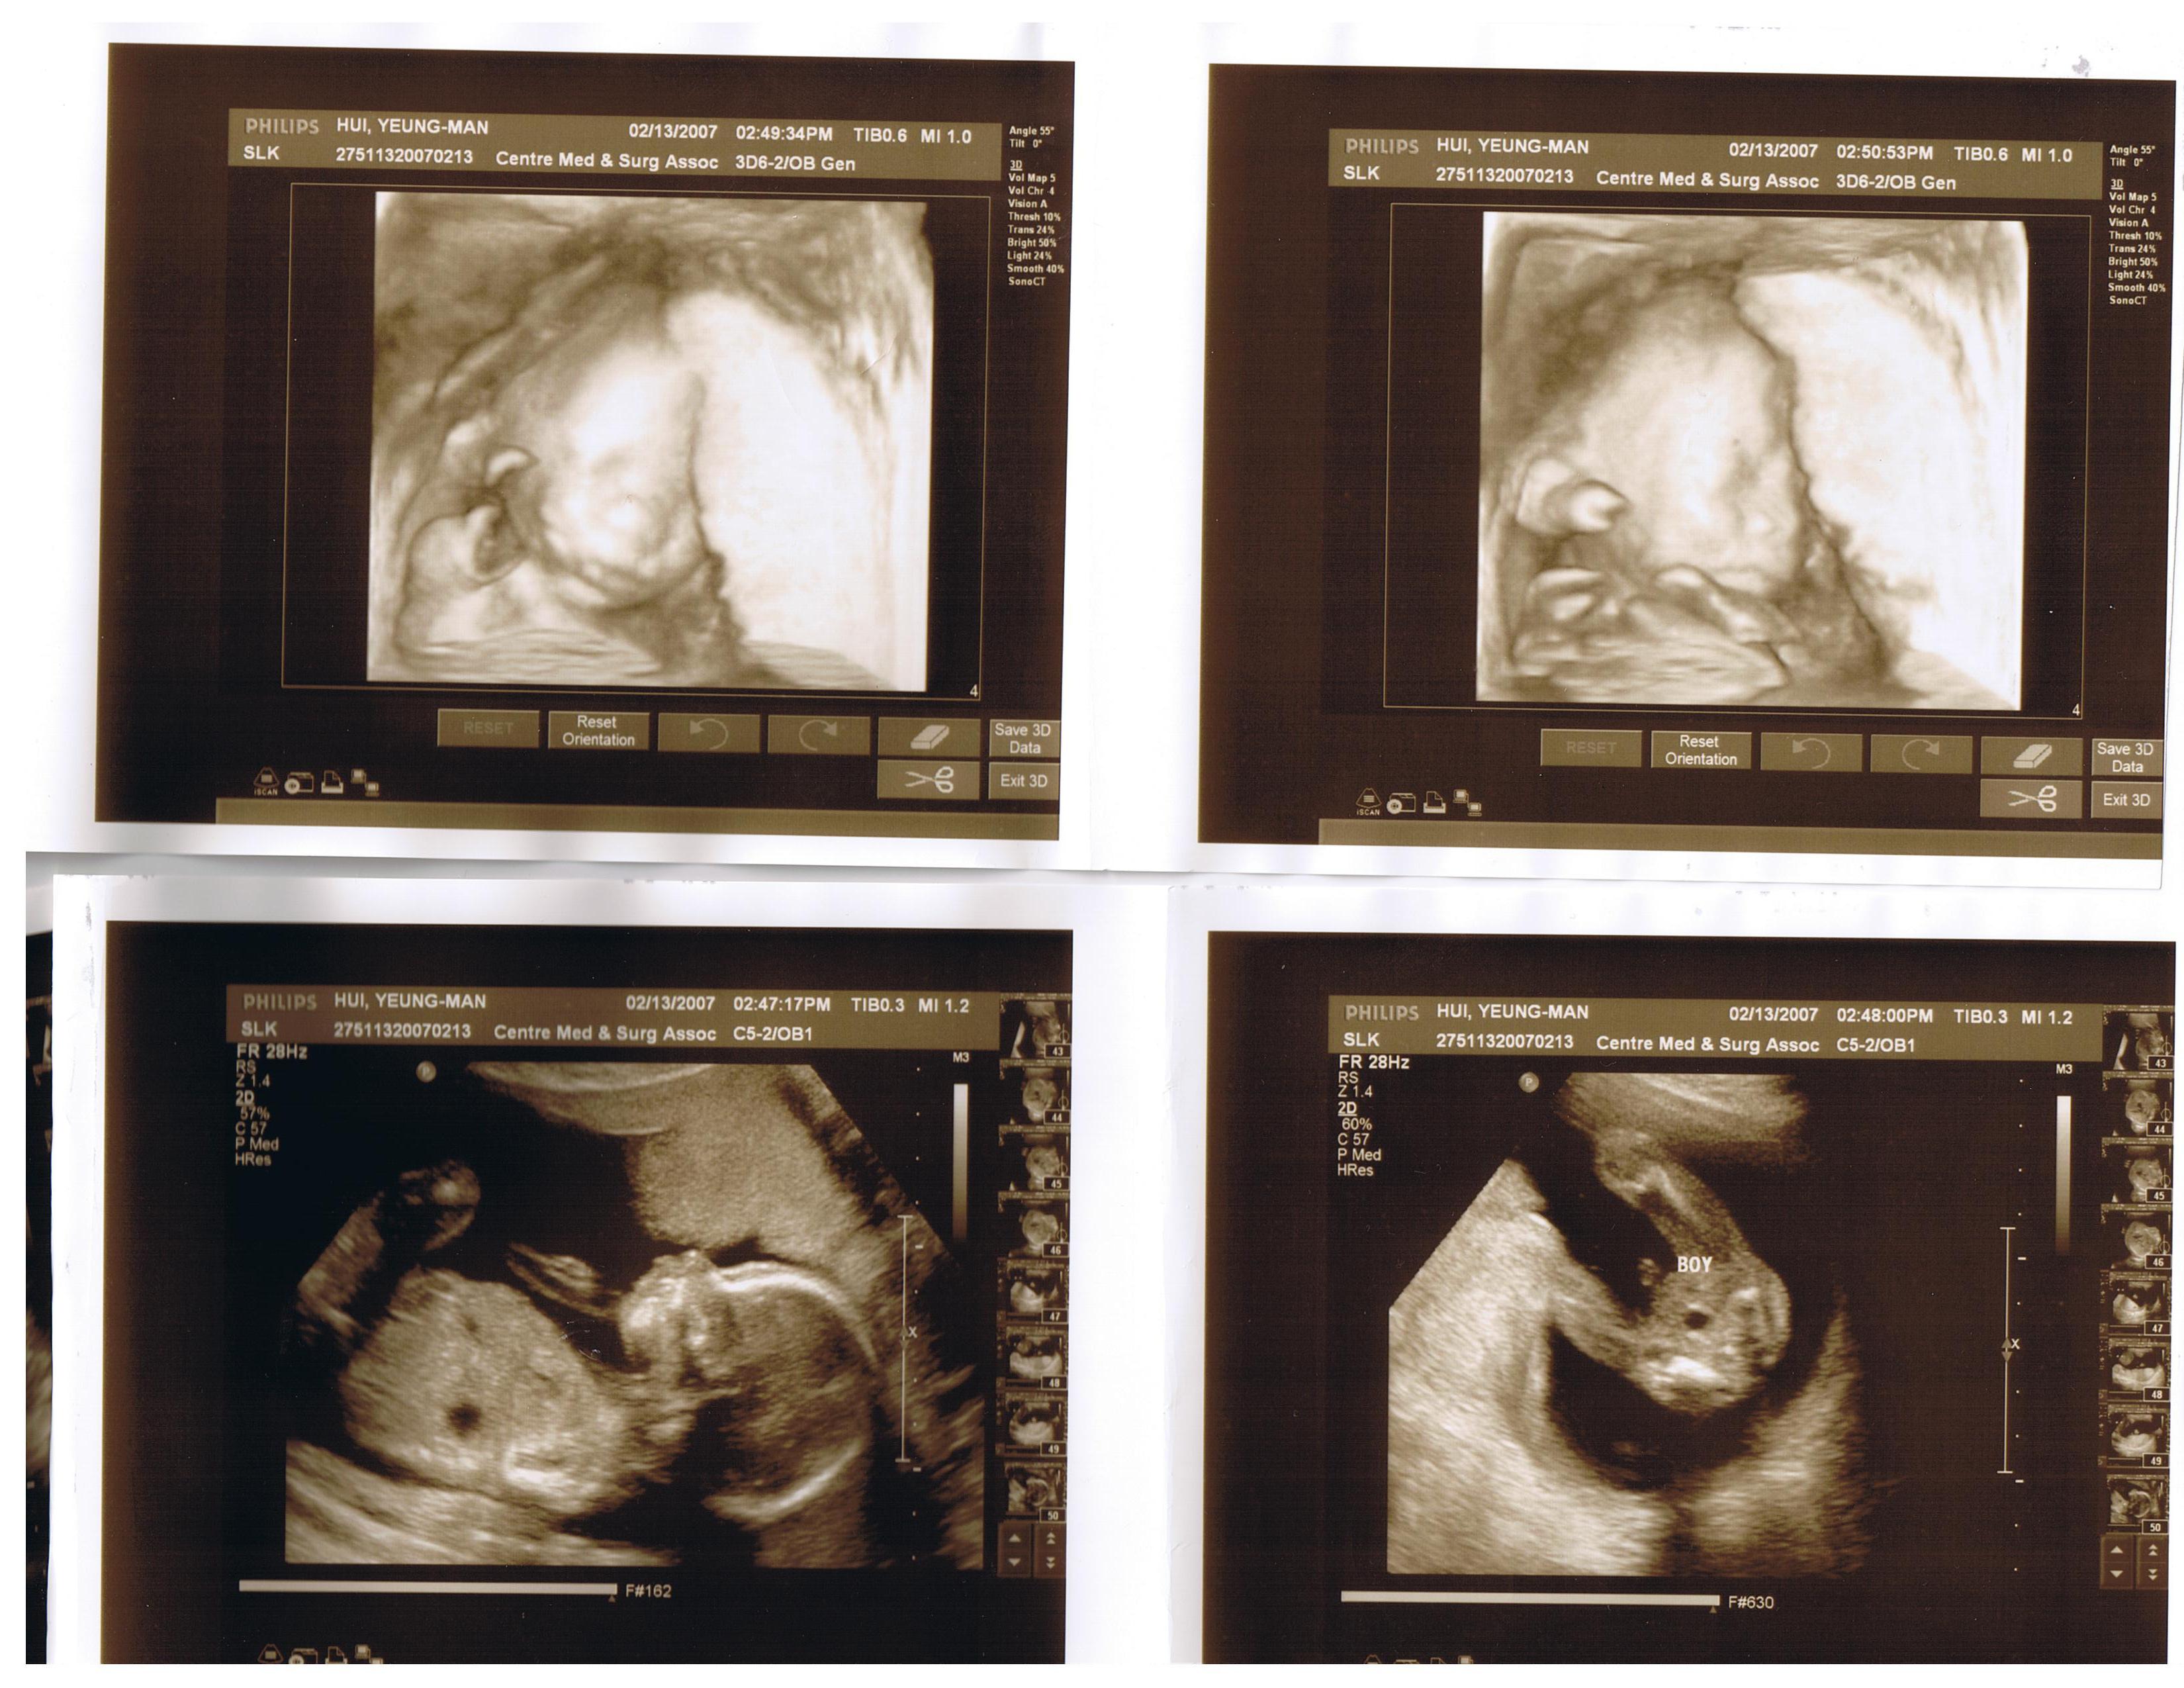

2月13日的情人節前夕, 是我跟老公大人等到脖子都長几吋的日子. 我們終於要跟寶寶作一次最詳細的接近了, 我們終於可以我們寶寶是男生還是女生了耶…….嘻…….好開心喔!

醫生看了一輪寶寶的骨骼之後, 終於問我們要不要知道寶寶的性別了. 然後就把鏡頭拉近放大, 指著寶寶的弟弟跟我們說:"this is a boy!" 哈哈哈……原來我們寶寶真的很合作, 把腳舉得高高的, 還張得大大的, 向我們show 他的弟弟耶….哈哈哈….從頭到尾都沒有藏過, 一路show 到底, 醫生就跟我們講了三, 四次—–這是寶寶的弟弟了, 哈….好可愛喔!

可是呢, 到醫生要看寶寶的小腦袋發育的時候, 他的臉可是藏起來了, 藏到低到不能再低, 醫生要用力的用手在我肚皮上按壓以讓寶寶能把姿勢倒過來, 讓我們能清楚的看到他的樣子, 不然就要利用內攝影機去幫助了, 還好, 按了三次之後寶寶就坐起來了, 讓我們可以看到他的樣子了, 不但如此, 他還一直動一直動, 讓醫生的探視器一直跟著他動…嘻….我們寶寶好活潑喔 ………………..

晚上, 我跟老公大人就一直拿著寶寶的超音波照片看, 在研究寶寶的額頭是像誰, 臉像誰, 為什麼我們寶寶的嘴巴好像有點大, 這又是像誰………拿著那張不算清晰的照片一直講個不停…………………哈哈哈………….

這几張照片蠻清楚的, 連我爸媽都會看喔, 我想大家都會看得懂吧.

第四那張是我們寶寶的小屁股喔, 醫生小姐還特意在那里注明, 看那里就知道我們是小男生了耶!!!!!!!!!